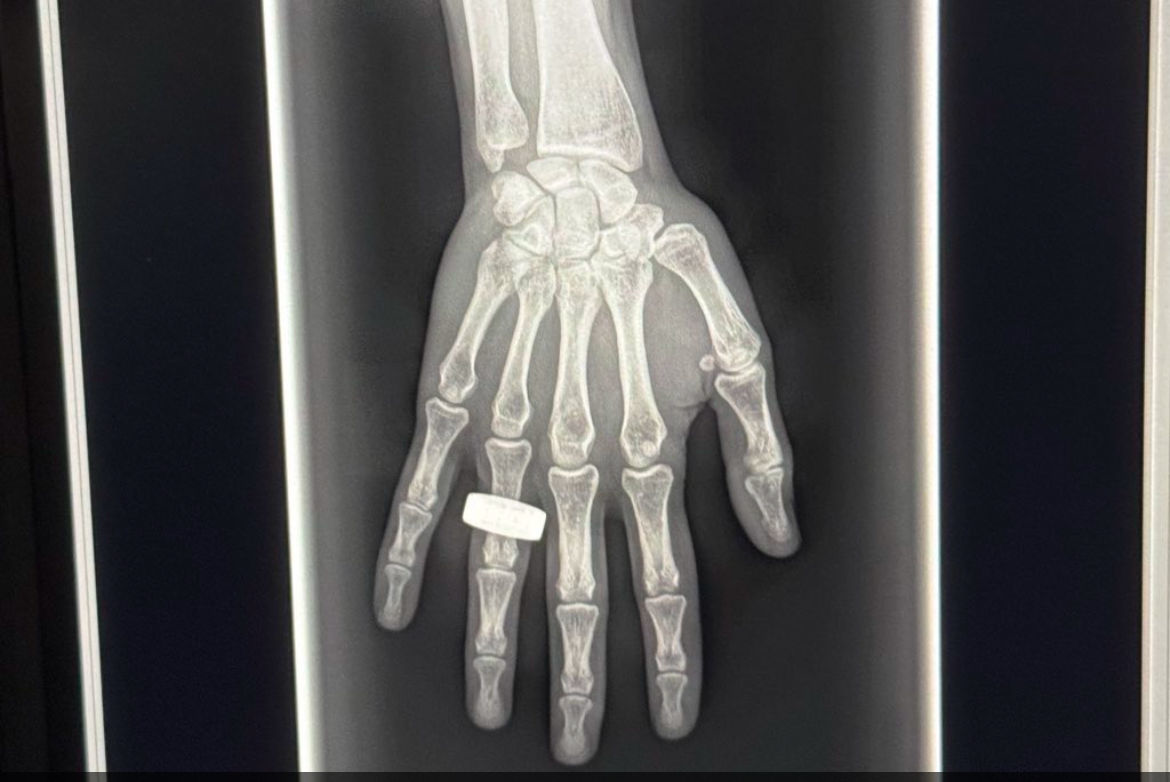

The Reveal Mobi Lite mobile imaging system, integrating SpectralDR technology and the Reveal 35C x-ray detector, which recently gained attention as part of the SpaceXray Project on the Fram2 mission, according to the vendor.

KA Imaging also noted that ongoing studies are exploring the use of the Reveal 35C detector for applications such as coronary calcium visualization and bone density measurement. The technology is not yet cleared for these uses.